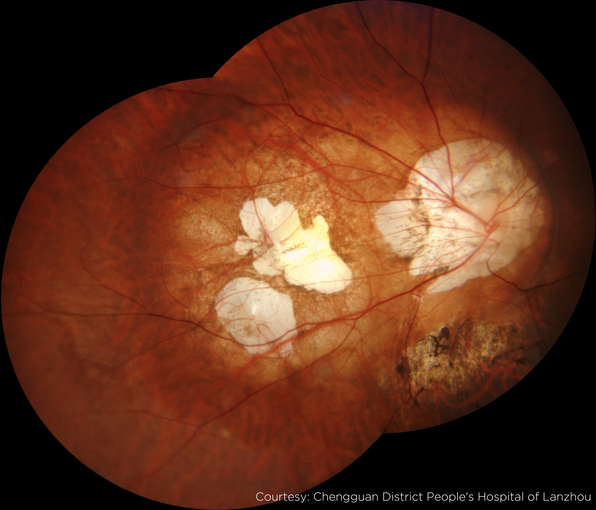

Image Gallery